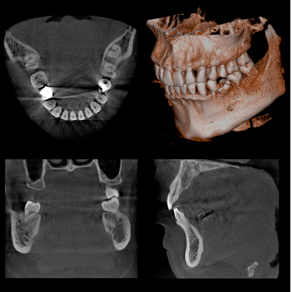

• 歯科用3D・CT

歯科用3D・CT

当院では、より安全で正確な診断と治療を行うために歯科用3D・CTを導入しています。

CTX線の照射量を抑えることで、従来よりも最大40%の被ばく量を軽減できる設計になっており、患者さまの身体への負担も最小限に抑えられます。全国でも導入率がまだ5%ほどの先進機器で、2Dのレントゲンでは確認できなかった情報も立体的に把握できるため、インプラント治療や神経の治療、親知らずの抜歯などにおいて、より高い安全性と確実性をもった治療を可能にします。